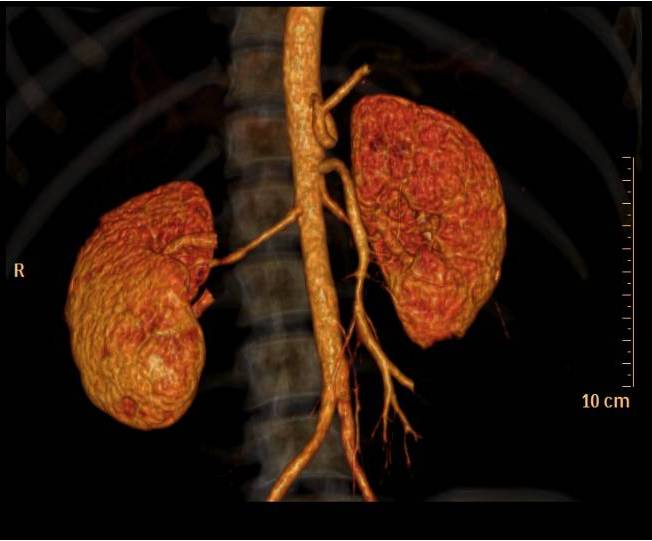

- CT angiography – Computerized tomography angiography (i.e. CTA) is increasingly being used to scan for fibromuscular dysplasia. Surprisingly, this technique is still not well validated, although better imaging techniques and reconstruction programs offer very good views of the renal arteries:

-

Renal Artery Fibromuscular Dysplasia

Fibromuscular dysplasia of the renal arteries is of particular interest because it is a cause of treatable reno-vascular hypertension and of renal function impairment (although renal failure is rare). Fibromuscular dysplasia of the renal arteries is a popular answer to the question: “what is a reversible cause of reno-vascular hypertension?”, though it probably accounts for less than 10% of such cases. Renal artery FMD tends to affect women more than men and the age range is usually 15-50. In almost 40 percent of women with renal artery fibromuscular dysplasia, the disease progresses with time. Of note – according to imaging studies, many patients have asymptomatic renal artery FMD. These patients may develop hypertension only if renal artery dissection occurs.